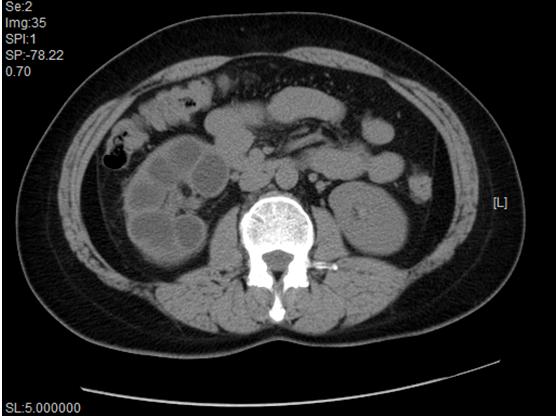

(3)CT和MRI:CT对中晚期肾结核能清楚地显示扩大的肾盏肾盂、皮质空洞及钙化灶,三维成像还可以显示输尿管全长病变。MRI水成像对诊断肾结核对侧肾积水有独到之处。